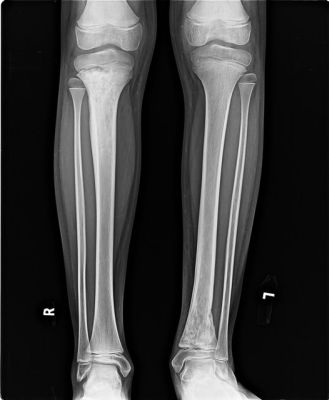

We do all X-Ray procedures like :